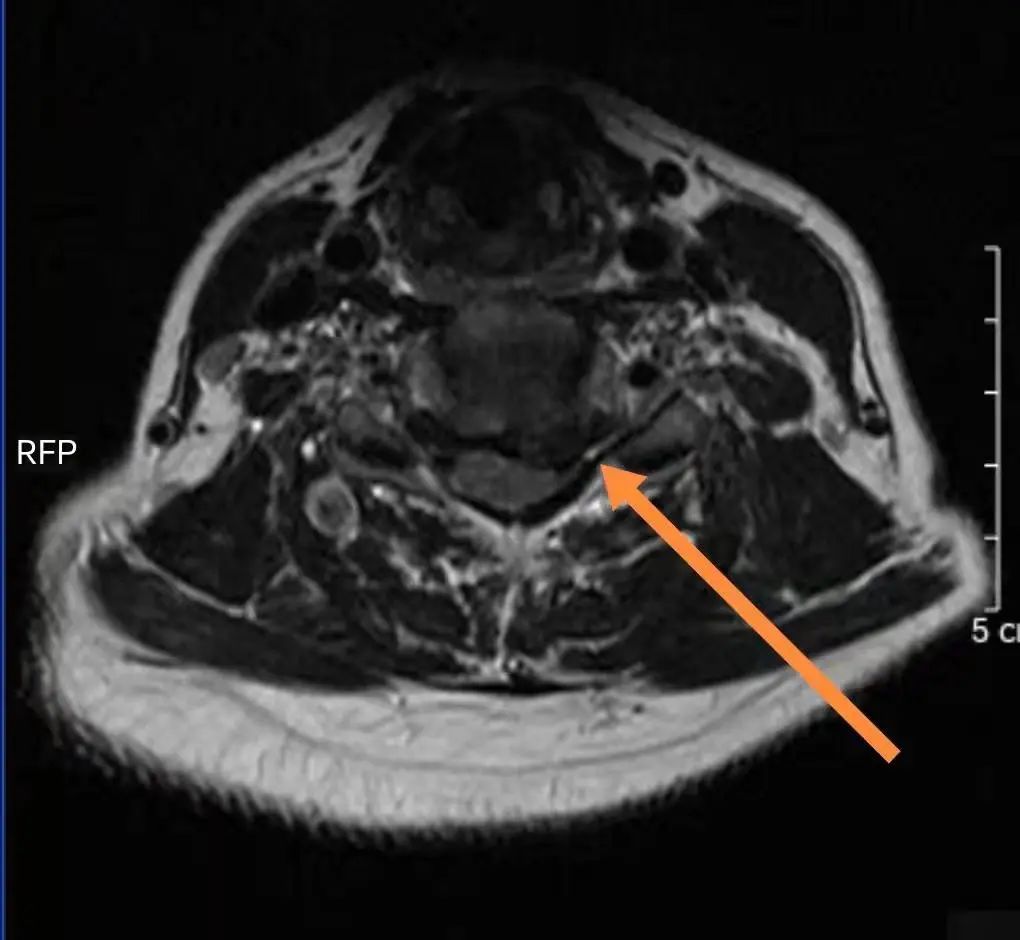

患者飽受神經根型頸椎病困擾數年,左上肢放射痛,痛如針刺,且腕背伸肌力降低至4級,坐臥不安。曾多次予針灸、口服藥物等保守治療,疼痛仍反復發作,沒有明顯改善。本次住院前一周,患者癥狀明顯加重,嚴重影響了日常生活,遂前來縣醫院就診。 入院后,骨科負責人、主任醫師陳如孫為其進行了詳細的查體,并仔細詢問病史,通過磁共振檢查發現:患者頸5-6椎間盤向左后方突出,明顯壓迫左側神經根,左側隱窩狹窄。